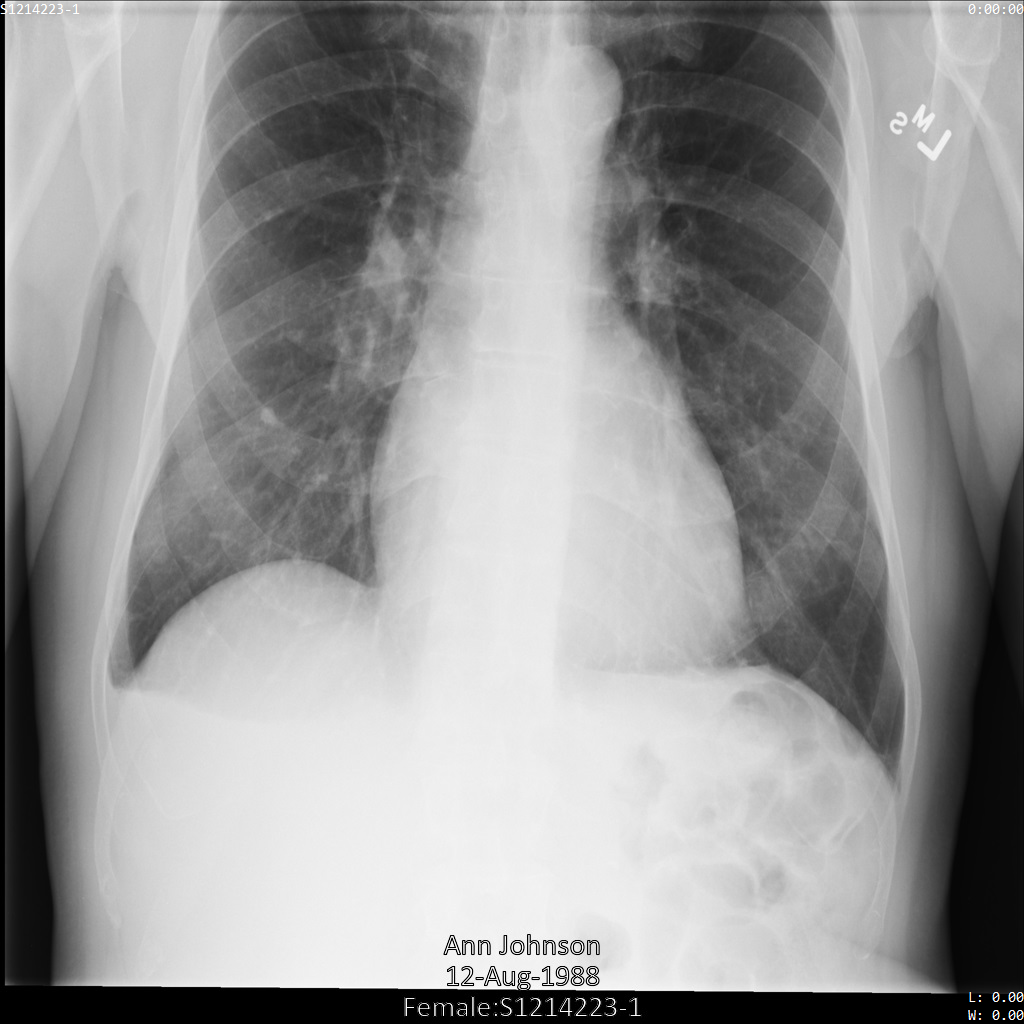

다음 각 섹션에서는 다양한 방법을 사용하여 DICOM 데이터를 익명화하는 방법을 설명합니다. 익명화된 이미지의 출력은 각 샘플에 제공됩니다. 각 샘플은 다음과 같은 원본 이미지를 입력으로 사용합니다.

각 익명화 작업의 출력 이미지를 이 원본 이미지와 비교하여 작업의 효과를 확인할 수 있습니다.

Cloud Healthcare API에 이미지를 제출하면 이미지가 다음과 같이 표시됩니다. 삭제 목록에 제공된 태그 외에 PatientBirthDate만 이미지에서 삭제됩니다. 이미지에 표시되는 메타데이터에 해당하는 삭제 목록의 유일한 태그이기 때문입니다.

이미지 상단의 PatientBirthDate는 removelist의 구성에 따라 수정되었지만 이미지 하단의 번인 PHI는 그대로 유지됩니다. 번인 텍스트도 삭제하려면 이미지에서 번인 텍스트 수정을 참조하세요.